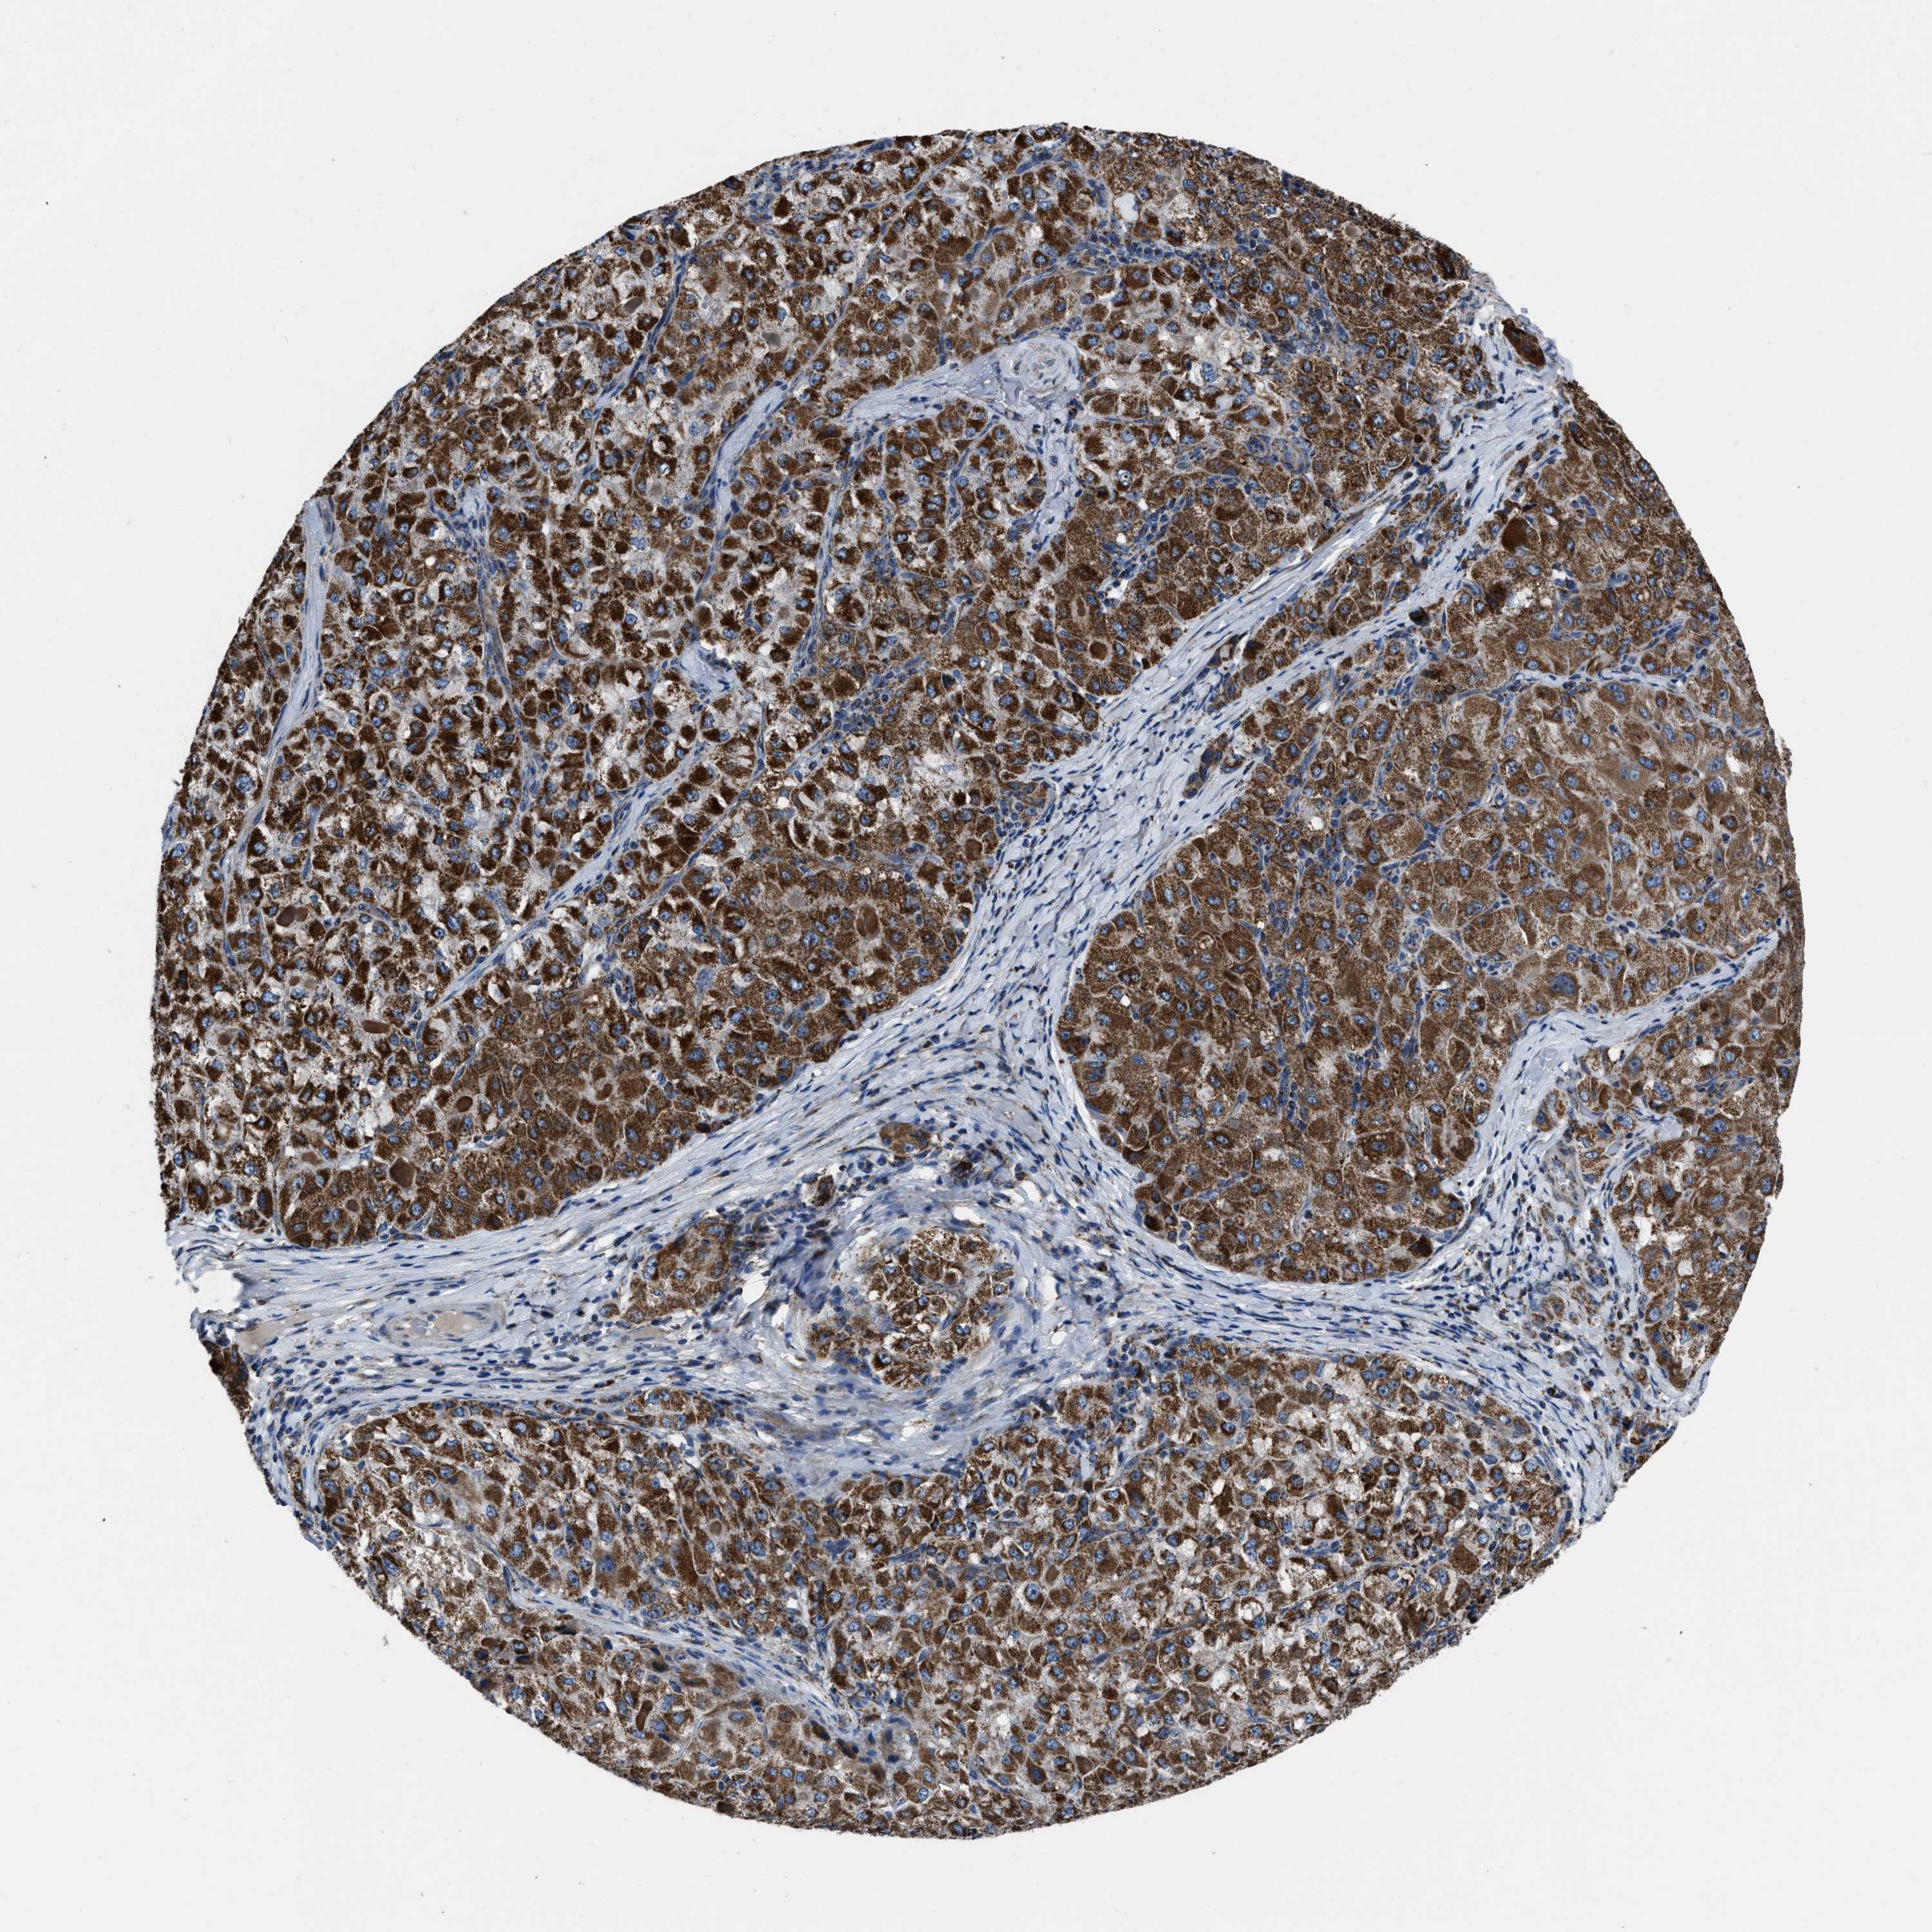

LIVER CANCER - Protein expressioni

A mouse-over function shows sample information and annotation data. Click on an image to view it in a full screen mode. Samples can be filtered based on level of antibody staining by selecting one or several of the following categories: high, medium, low and not detected. The assay and annotation is described here.

Note that samples used for immunohistochemistry by the Human Protein Atlas do not correspond to samples in the TCGA dataset.

Antibody stainingi

Antibody staining in the annotated cell types in the current human tissue is reported as not detected, low, medium, or high, based on conventional immunohistochemistry profiling in selected tissues. This score is based on the combination of the staining intensity and fraction of stained cells.

Each image is clickable and will lead to virtual microscopy that enables deeper exploration of all samples and also displays staining intensity scores, fraction scores and subcellular localization as well as patient and tissue information for each sample.

Antibody HPA018893

Staining

High

Medium

Low

Not detected

Intensity

Strong

Moderate

Weak

Negative

Quantity

>75%

75%-25%

<25%

None

Location

Nuclear

Cytoplasmic/membranous

Cytoplasmic/membranous,nuclear

Cholangiocarcinoma

Carcinoma, Hepatocellular, NOS